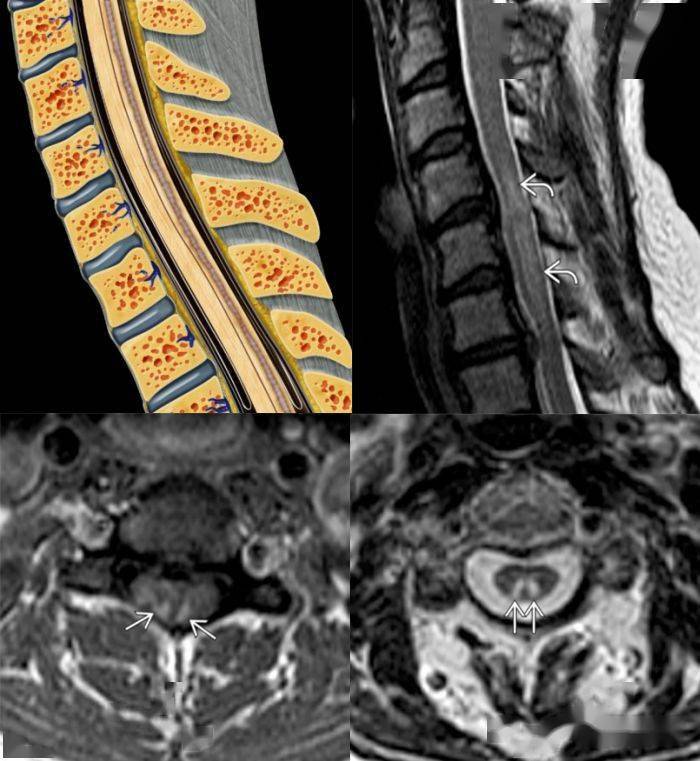

脊髓前动脉最多见 mri: 前 2/3 脊髓(脊髓前动脉);双侧灰质前角

2/3 梗死,dwi 提示细胞毒性水肿脊髓前动脉梗死导致双侧灰质前角梗死